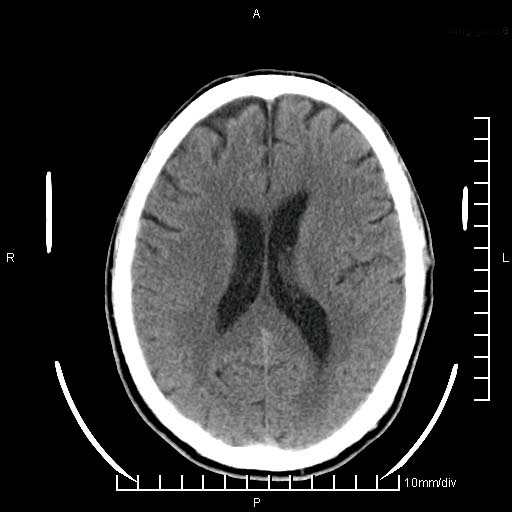

临床以双下肢浮肿,疼痛收治,无明显神经系统症状,既往无梗塞,出血病史。左颞叶见低密度灶,考虑什么?

考虑左侧颞叶脑软化灶。

无强化 无占位 软化灶吧

无强化、 无占位、局部脑沟增宽, 软化灶吧。